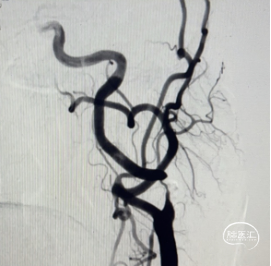

术前DSA。

左侧正侧位造影。

DSA可见:左侧颈内动脉C1段重度狭窄,狭窄率约90%。

然后通过保护伞导丝将支架输送到位,并顺利释放。造影见狭窄解除,血流通畅。回收装置顺利回收保护伞,观察保护伞内未见明显栓子。术后正侧位造影提示狭窄段开放,支架贴壁良好,支架处残余狭窄率小于10%,无血管夹层,左侧颈内动脉充盈较术前迅速,血管走形、形态未见明显异常。